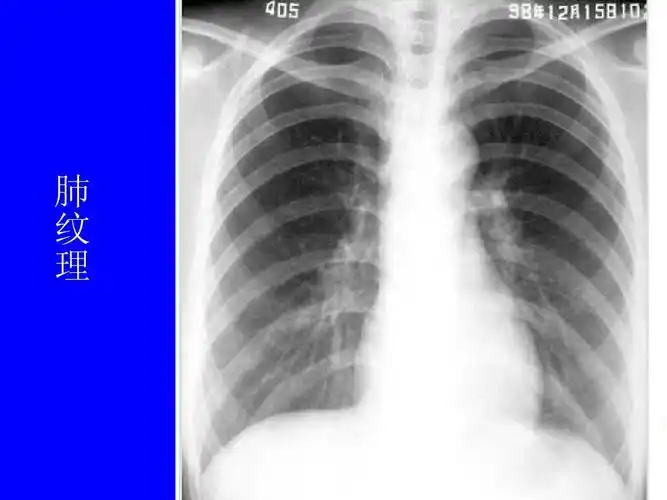

肺野的划分在正常时,下肺野纹理比上肺野多而粗,而右下肺野肺纹理比左

肺部疾病影像学阅片 一,正常胸片 正常胸片(正位片)